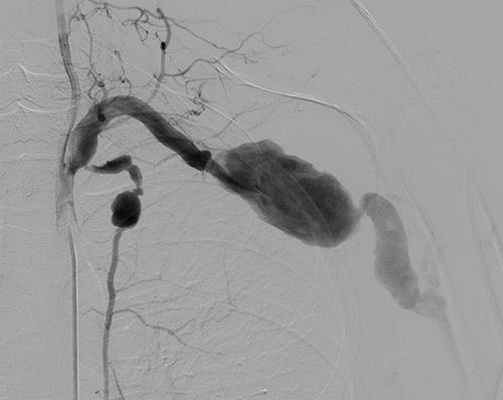

МСКТ аорты и артерий нижних конечностей: аневризма правой ОПА диаметром 38 мм на протяжении 76 мм, правой общей бедренной артерии (ОБА) диаметром 26 мм, протяженностью 58 мм с наличием пристеного тромбоза, а также тромбированной аневризмы подколенных артерий. Слева концентрическая пристеночно тромбированная аневризма дистального отдела поверхностной бедренной артерии, подколенной артерии диаметром 36 мм, длиной 40 мм. Диаметр аневризмы правой подколенной артерии 47 мм на протяжении 50 мм (рис. 1). Рисунок 1. Мультиспиральные компьютерные томограммы аорты и артерий нижних конечностей. Аневризма правых ОПА и ОБА. а - фронтальный срез. Рисунок 1. Мультиспиральные компьютерные томограммы аорты и артерий нижних конечностей. Аневризма правых ОПА и ОБА. б - сагиттальный срез.

ДС артерий нижних конечностей от 19.04.12: справа аневризма ОПА (диаметр 34,6 мм), аневризма ОБА (22,4 мм). Протезированная подколенная артерия, шунт проходим, в дистальных отделах голени кровоток магистрального типа.